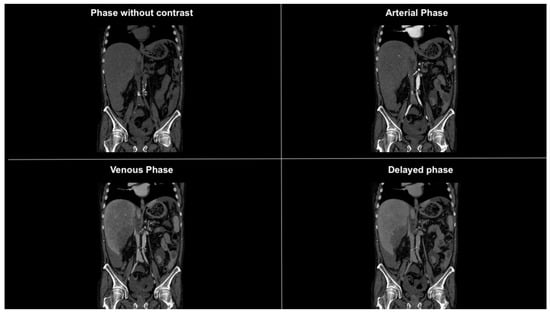

Figure 2. Coronal CT images in different phases showing subdiaphragmatic fluid collection bilaterally, within the paracolic gutters, and prominently around the liver. The fluid collection is suggestive of hemoperitoneum.